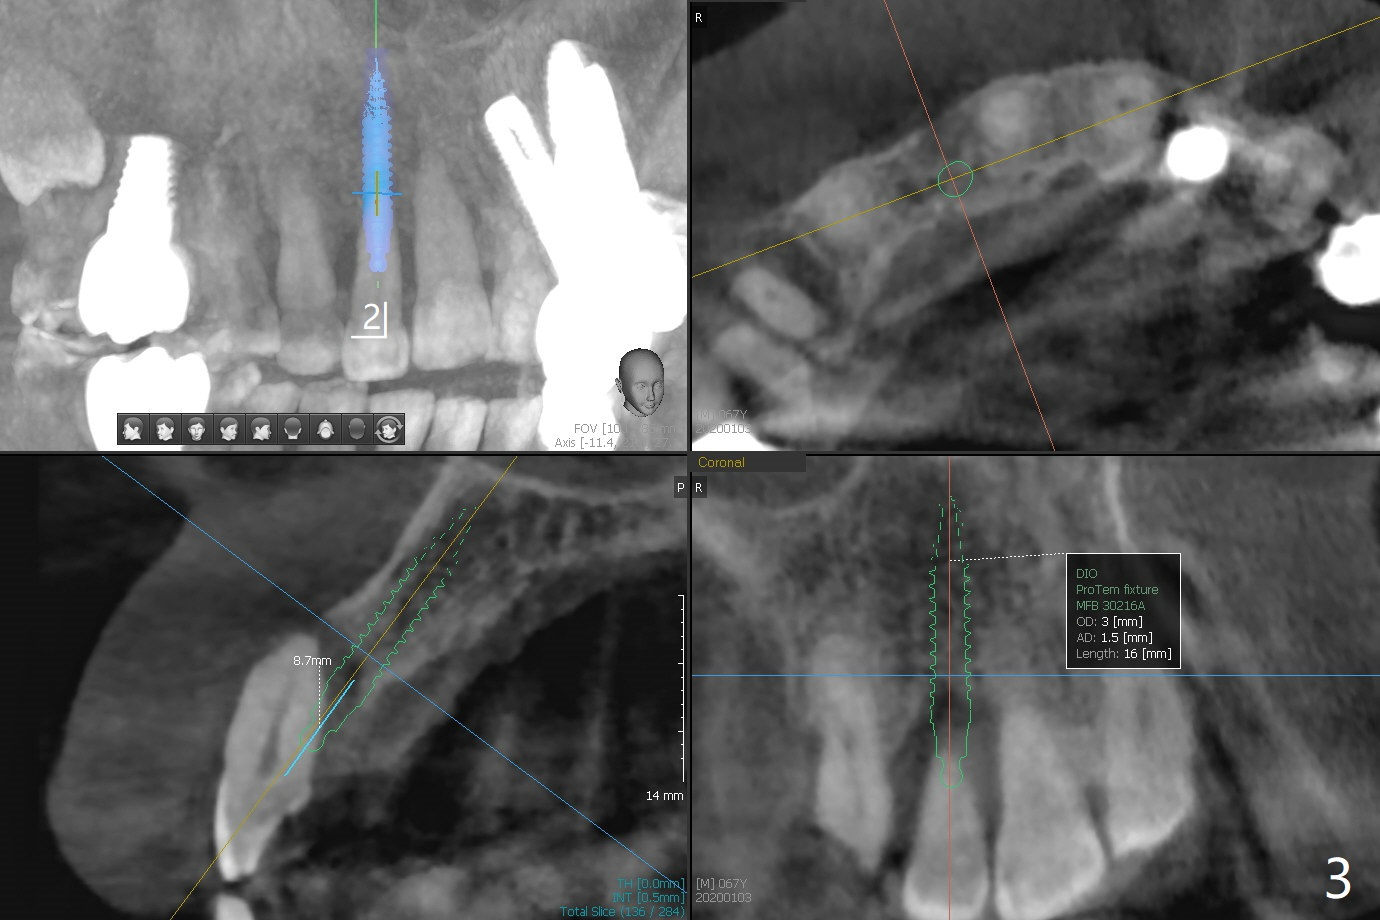

68岁男要求拔除右上2松动牙(图一),尽管近远中空间大,不能象左上2种大植体(图二,五)。右上2骨质吸收严重,植体应该植入深,牙龈厚(6毫米,图三,四),需要长基台,放置粘性骨粉修复骨质缺失。PRF膜好像用处不大,PRF上清液适当多用于制作粘性骨粉。准备牙周洁治器和Endogain,让骨粉与邻牙牙根结合。